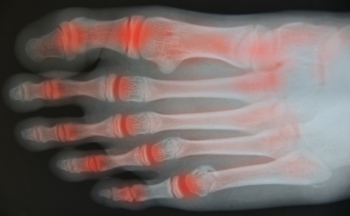

Causes and Relief From Toe Arthritis

Toe arthritis is a condition where the joints in the toes become inflamed, causing pain and stiffness. The most common cause is osteoarthritis, which occurs as the cartilage in the toe joints wears down over time, often due to age or repetitive stress. Other causes include rheumatoid arthritis or injury to the toe. Symptoms of toe arthritis include pain in the affected joint, particularly during movement, swelling, and a reduced range of motion. In some cases, the joint may become deformed or misaligned. Relief from toe arthritis involves wearing proper footwear that provides support and cushioning, as well as anti-inflammatory medications to reduce pain and swelling. Specific exercises can also help improve joint flexibility and strength. In severe cases, surgical options may be considered to restore function and alleviate pain. If you have symptoms of arthritis in your toes, it is suggested that you consult a podiatrist who can offer you effective relief and management tips.

Arthritis is a joint disorder that involves the inflammation of different joints in your body, such as those in your feet. Arthritis is often caused by a degenerative joint disease and causes mild to severe pain in all affected areas. In addition to this, swelling and stiffness in the affected joints can also be a common symptom of arthritis.